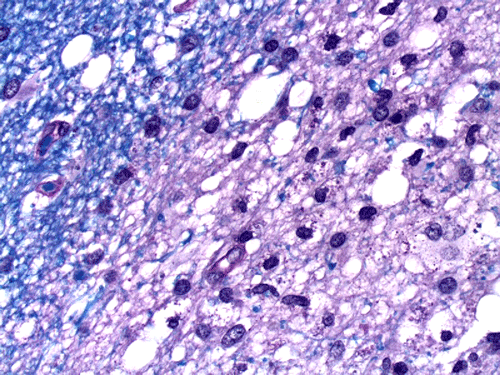

On CT scan, there is multiple hypodense white matter lesions that appear to spare a thin layer of subventricular white matter (Panel A). The T2-weighted images on MRI provides a more accurate estimation. The white matter in the occipital lobes is most affected (Panel A). There is extensive vacuolar changes in the white matter (Panel B and C) and there is a questionable increase in cellularity. In some of the thin walled blood vessels, there is a thin layer of perivascular lymphocytic infiltration which is free of atypia (Panel D, E, and F). The lymphocytes do not appear to extends into the parenchyma. On higher magnification, some large reactive astrocytes can be seen (Panel G). In a minority of areas, some concentric rings can be seen on hematoxylin-eosin stained sections (Panel H). These rings appear to be alternating rings of myelinated and demyelinated white matter and the vacuolar changes appear to be limited mainly to the concentric lesions. The adjacent myelinated areas are spared (Panel I). In some areas, the level of myelin loss appears to be proportional to the level of vacuolar changes (Panel J and K). On immunohistochemistry for glial fibrillary acidic protein (GFAP), the degree of gliosis is also more impressive in areas with more prominent vacuolar changes (Panel L and M). The vacuolar areas also appear to have a reduced density of axons (Panel N). Axonal spheroids are also present in these areas (Panel O). Although a prominent infiltration of foamy histiocytes is not noted on hematoxylin-eosin stains, immunohistochemistry for CD68 illustrated positive cells in a minority of demyelinated areas (Panel P). These cells lacks the foamy nature of macrophages and their morphology would suggest microglial cells. The reactive astrocytes are not immunoreactive for CD68 (Panel Q). Immunohistochemistry for T-cells (CD3) and B-cells (CD20) demonstrates only a thin rim of perivascular infiltration without significant extension into the surrounding parenchyma (Panel R, S, and T).

Pathology

On histology, there are extensive spongiform degeneration and vacuolar degeneration of the deep white matter associated with variable macrophage, profound axonal loss, degenerating axons with spheroid formation and evidence of axonal injury in adjacent normal appearing white matter  1, 2, 3, 4. Demyelinating changes featured by lost of myelin and infiltration of macrophages have also been described  1,  2, 5,  6. Under the electronic microscope, there are vacuolar degeneration of the oligodendroglia, swollen mitochondria and distended endoplasmic reticulum.